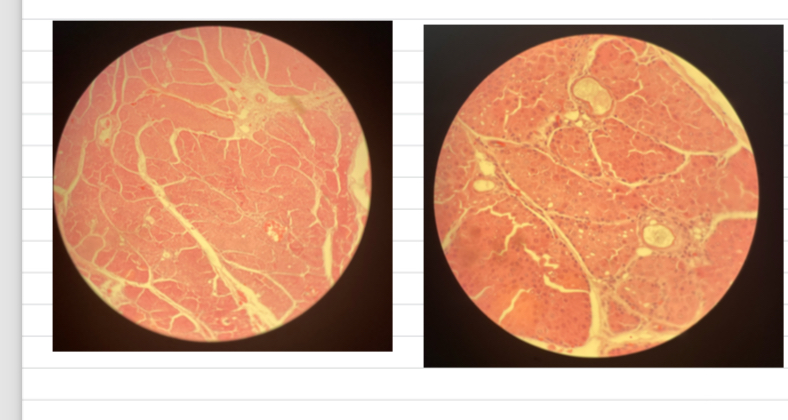

Lipoma

- mature adipocytes (appearance like normal fat)

- NO mitotic figures + rare CT w/ bvs

- nucleus eccentric (@ side)

Liposarcoma

- small + large adipocytes

- haemorrhages + necrosis

- highly cellular w/ mitotic figures